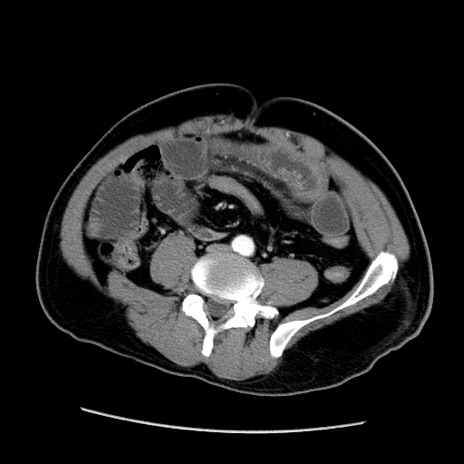

症例22(横断像)

【症例】50歳代男性

【主訴】腹痛

【現病歴】AVMからの被殻出血のため回復期リハ病棟入院中。 本日午後3時頃急に下腹部痛が出現した。

【既往歴】AVM、被殻出血、虫垂炎、高血圧

【身体所見】意識晴明、左半身不全麻痺、会話の理解は良好、36.5°C、腹部:膨隆、全体に板状硬、下腹部正中に圧痛点あり、反跳痛-、筋性防御不明、右下腹部にope scar

【データ】WBC 9400、CRP 0.06